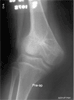

This is a case of a 16 year old male with a marked valgus deformity of the right knee. Two years prior to consult, the patient sustained a closed Salter Harris type 2 fracture of the distal femur when he was bumped by a vehicle. The injury was treated by open reduction and cross pinning using Steinmann pins. The knee progressively became deformed.

Physical examination: 45 degree genu valgus with the Q angle at 15 degrees Patellar was dislocated and not reducible True length discrepancy of 5 centimeters

Radiographs: Arrest of the lateral femoral physis The tibio-femoral angle was measured to be 34 degrees Patella dislocated laterally